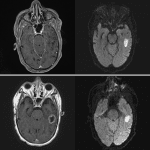

Age: 80

Sex: Male

Indication: Meningitis

Case #23

Findings

- Area of T2/FLAIR signal hyperintensity centered in the left inferior temporal gyrus with mild gyral expansion and associated central restricted diffusion and faint peripheral enhancement. Faint T2 hypointense rim about the area of restricted diffusion in the left temporal lobe

- Additional areas of FLAIR signal hyperintensity and restricted diffusion within left parietooccipital sulci as well as layering in the occipital horns of the bilateral lateral ventricles with mild diffuse dural thickening and enhancement

- Fluid signal in the bilateral middle ears and mastoid air cells

- Patchy periventricular T2/FLAIR hyperintensity

- No acute hemorrhage or hydrocephalus

Diagnosis

- Cerebritis

Findings concerning for late cerebritis/early abscess in the left inferior temporal gyrus with evidence of meningitis and ventriculitis. These findings likely represent a complication of left ostomastoiditis given proximity, which could be further evaluated with contrast-enhanced temporal bone CT. Recommend ENT and neurosurgical consultation.

Mild associated mass effect without midline shift, herniation, or hydrocephalus. No acute hemorrhage.

Patchy periventricular T2/FLAIR hyperintensity is nonspecific but commonly attributable to chronic small vessel disease.